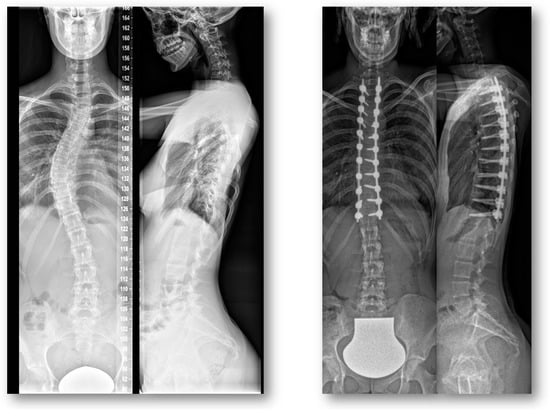

Return to Sport after Adolescent Idiopathic Scoliosis (AIS) Correction Surgery: A Retrospective Data Analysis

2.3. Radiographic Assessment

3.4. Clinical Outcome